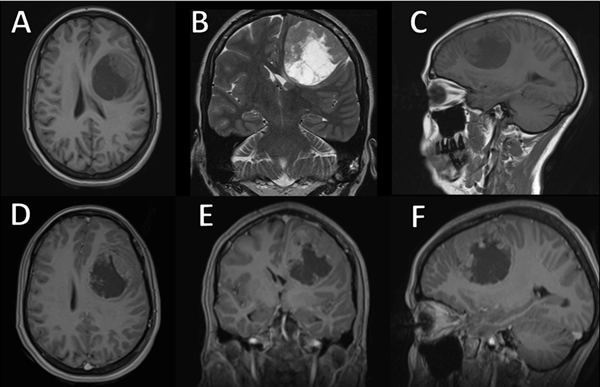

Se efectuó control a los seis meses postquirúrgicos sin evidencia de remanente tumoral ni progresión de la enfermedad (Figura 5). No requirió tratamiento oncológico adyuvante y, al no presentar crisis convulsivas posterior a la intervención, se optó por descender paulatinamente las dosis de anticomiciales hasta su suspensión.

Figura 5. Resonancia magnética cerebral postquirúrgica. A-C) Seis meses posteriores a la intervención, se evidencia la restitución completa del ventrículo lateral izquierdo y del parénquima cerebral circundante, sin evidencia de remanencia tumoral. D-F) No se observan realces patológicos a la administración de contraste endovenoso.